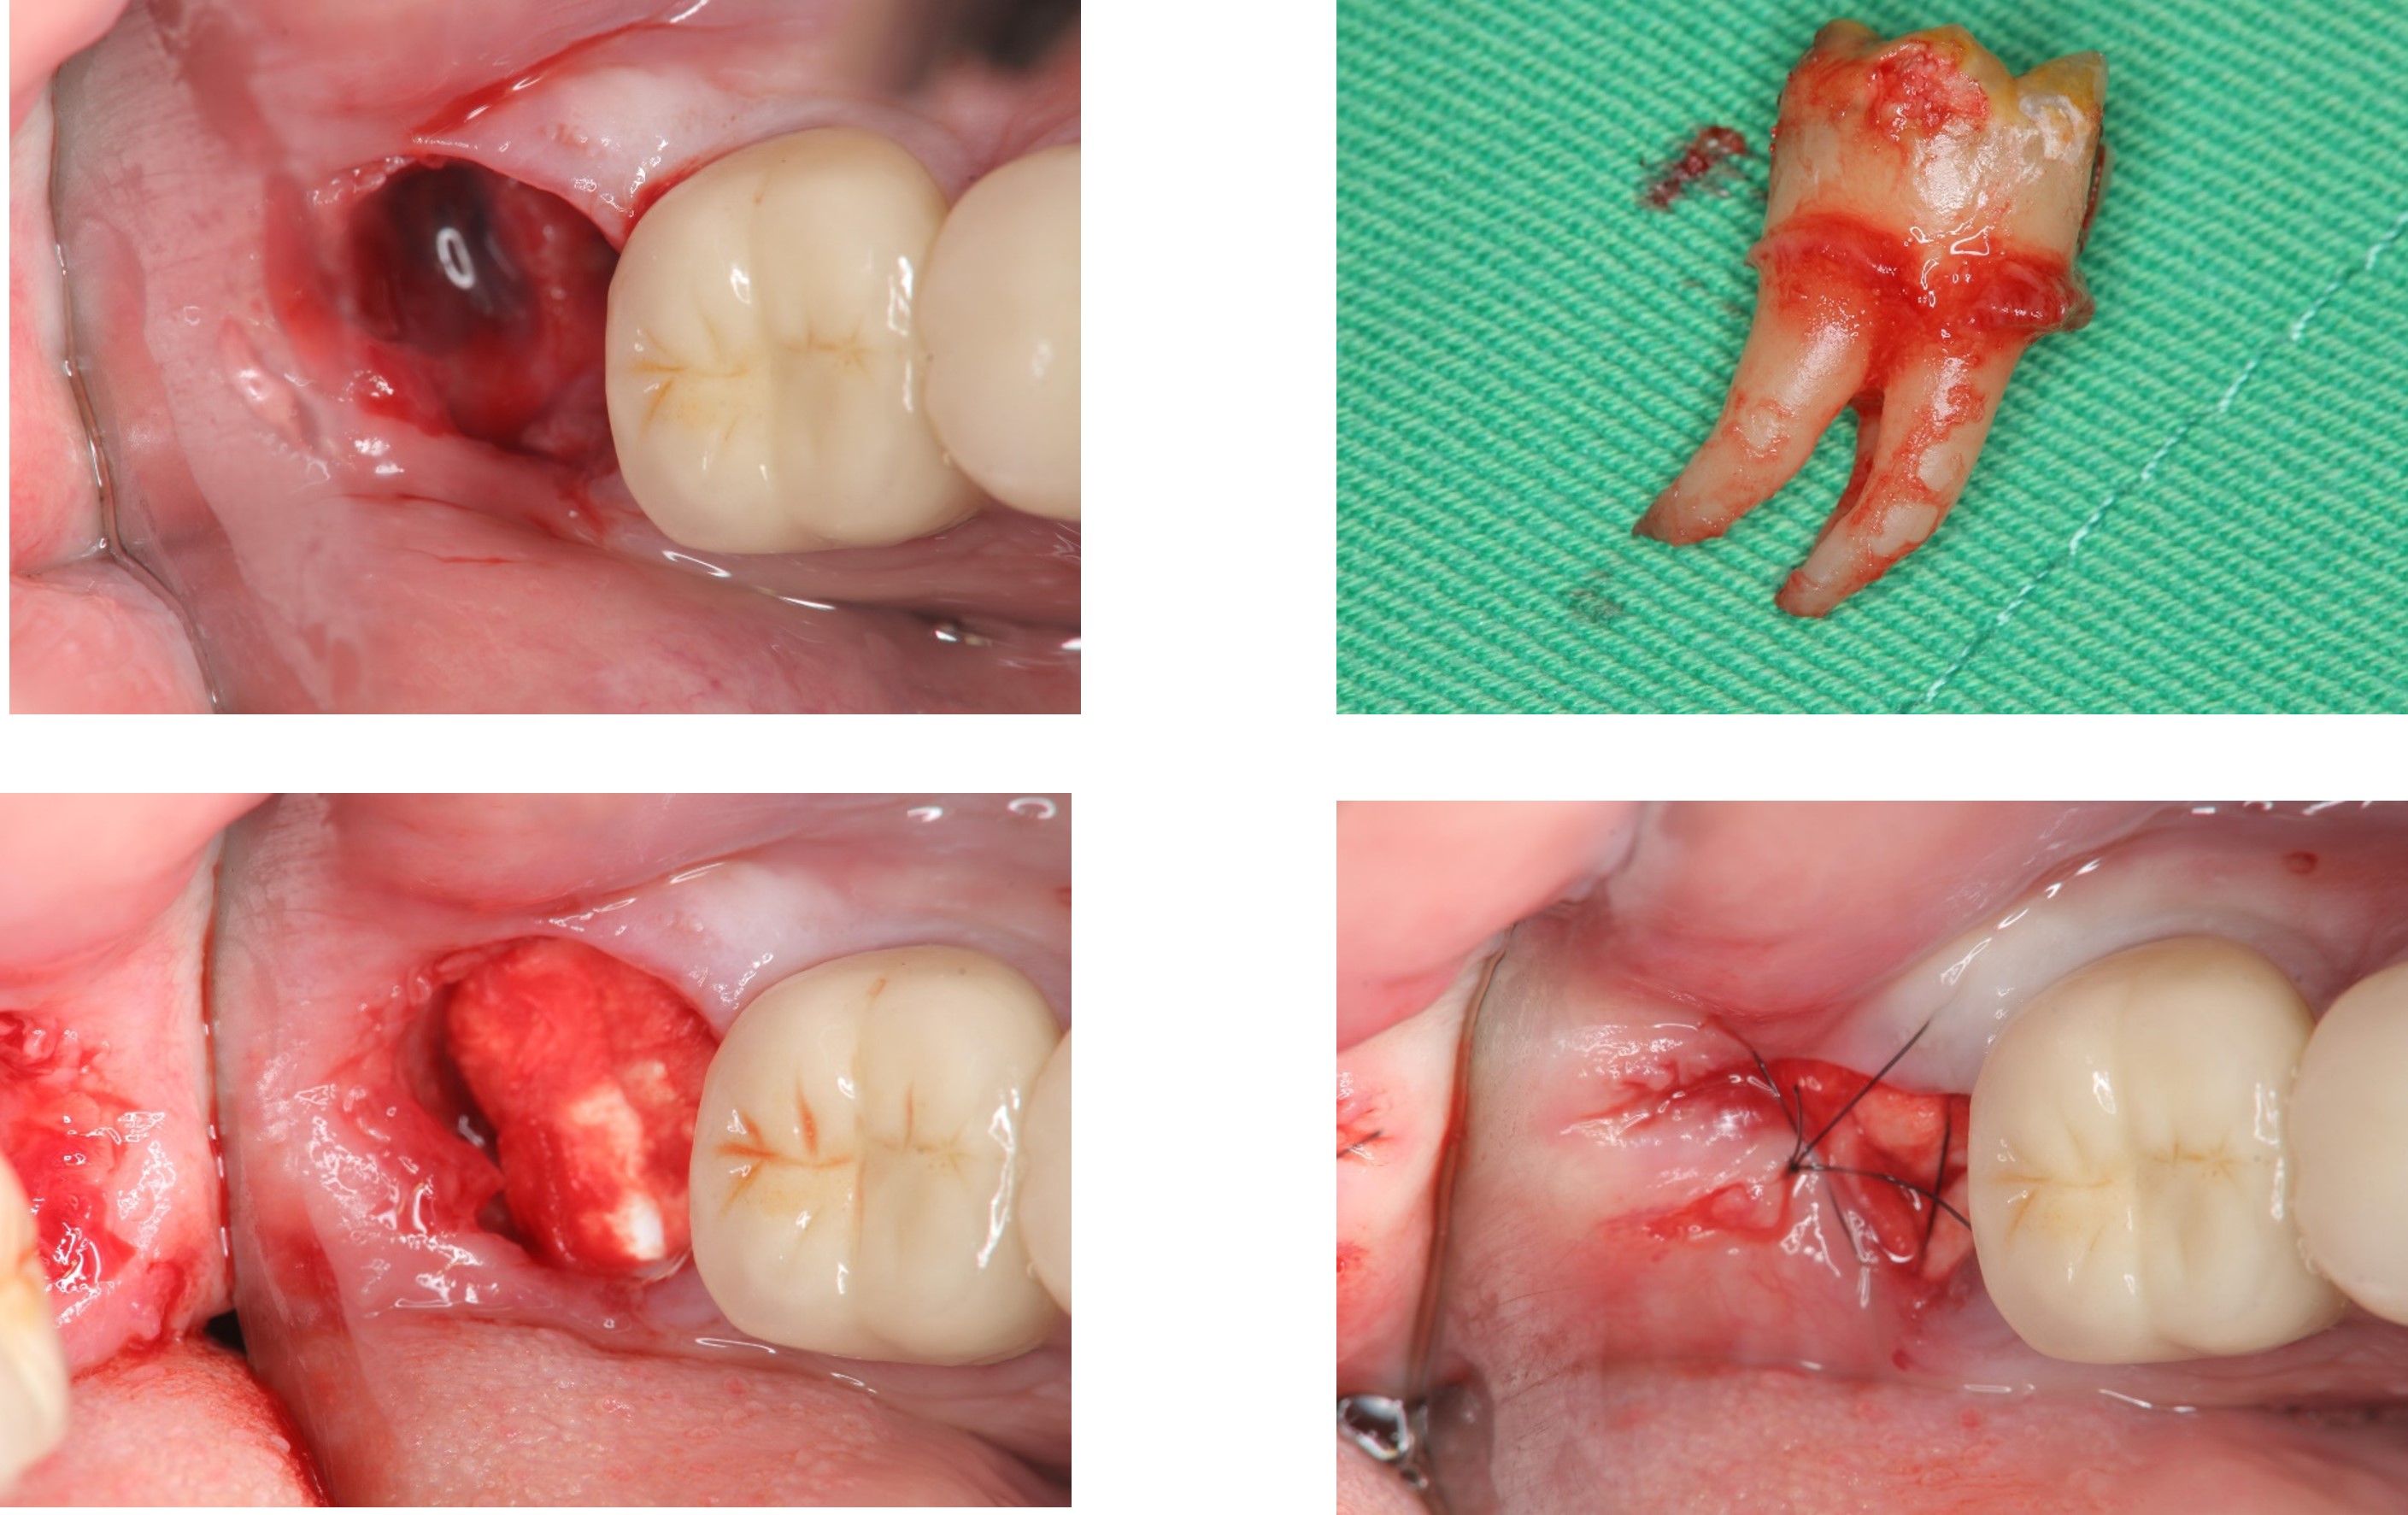

以水雷射切割皮瓣止血、再以手機等拔除阻生齒,並縫合之

1週後傷口癒合良好

使用骨質增生膠原蛋白,來處理拔牙後的傷口。此材料適用的範圍不僅用於拔牙後傷口,所有顎骨中的病灶於手術後皆建議使用。

1 、止血效果:特殊生物材料,能立即止血,且無血塊脫落之困擾。

2、減痛效果:加速傷口癒合,有效減輕疼痛

3 、預防效果:健全牙周組織,避免鄰近牙齒產生牙周病及乾性齒槽炎